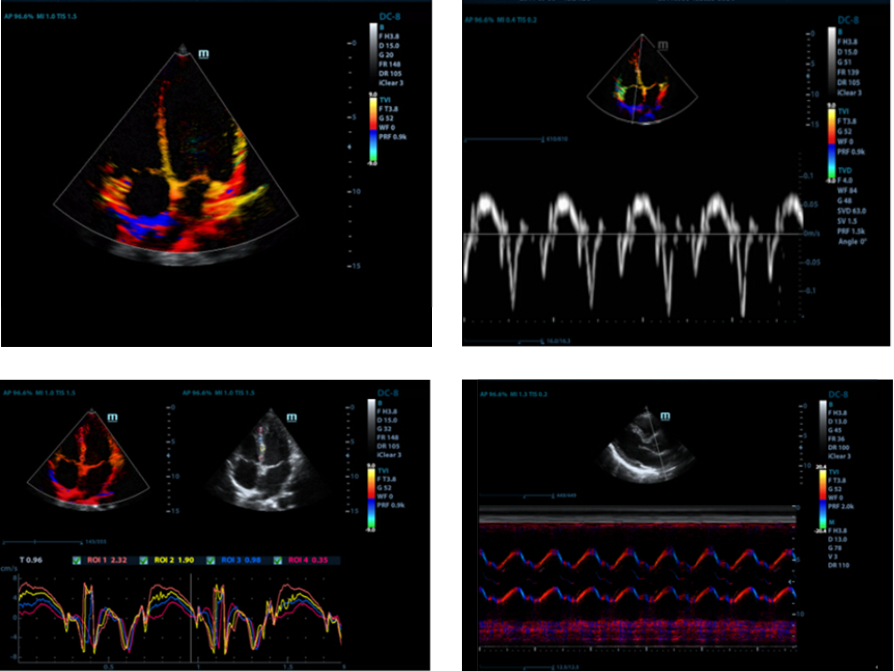

Free Xros M?

?rnek hatlar?n? her hangi bir a??ya ?zgĂŒrce yerle?tirerek kesin bir anatomik g?zlemin kazan?lmas?. 3 ?rnek hatt?n?n ayn? anda g?rĂŒntĂŒlenmesi sayesinde daha iyi g?rĂŒntĂŒlere ula??lmas?.

Free Xros CM?

Farkl? fazlarda miyokardiyal hareketin kesin olarak de?erlendirilmesi ve ayn? anda miyokardiyal senkronizasyonun belirlenmesi. YĂŒksek ?er?eve oran? ile kesin sonu?lar?n al?nmas?.

TDI

Doku Doppler G?rĂŒntĂŒleme, daha h?zl? ve do?rudan te?hisler i?in tĂŒm TDI modlar?n? sa?layarak, yerel miyokardiyal hareketi ve ?al??may? nicel olarak de?erlendirmeye izin verir.